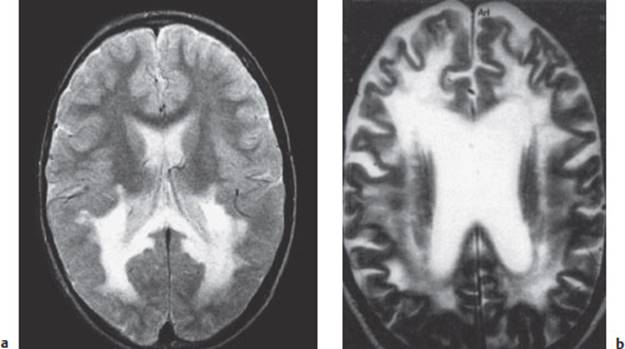

If the patient survives, MRI may reveal a permanent injury to the brain parenchyma (Fig. 6.3). The late posttraumatic symptoms resemble those of concussion, but they are more intense and usually persist longer. For further details, see p. 91.

Fig. 6.3 Parenchymal defects 6 years after brain contusion. The T2-weighted MR images reveal cortical defects in the left temporal (a) and frontal lobes (b), accompanied by signal changes in the underlying white matter.